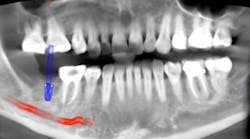

Radiographic evidence of bone loss is best determined with adequate and current radiographs,1 most typically a full-mouth periapical survey, including horizontal or vertical bitewings. Radiographic evaluation of the distribution and severity of bone loss, bone density, root anatomy, and approximation to other teeth provides specific information that will help in determining a proper diagnosis of the patient.1 The ADA recommendations for providing radiographs can be found in the table below.